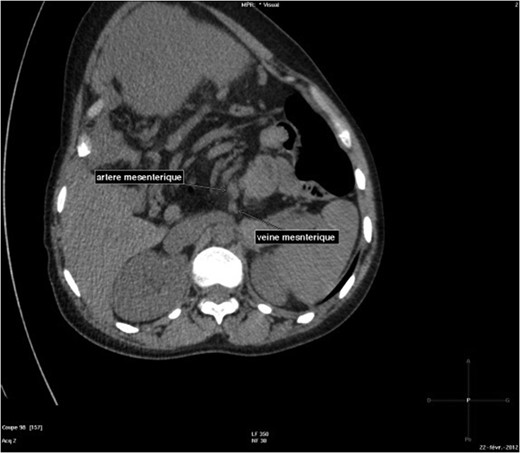

The abdominal-pelvic CT-scan showed a pre-splenic left position of the caecum and right colon, with no part of the colon on the right. The radiologist concluded that the patient was suffering from a complication of intestinal malrotation (IM) (Figs 1, 2, 3).

Abdominal-Pelvic CT-scan, non-contrast enhanced, in the sagittal plan, tenth dorsal vertebra level.